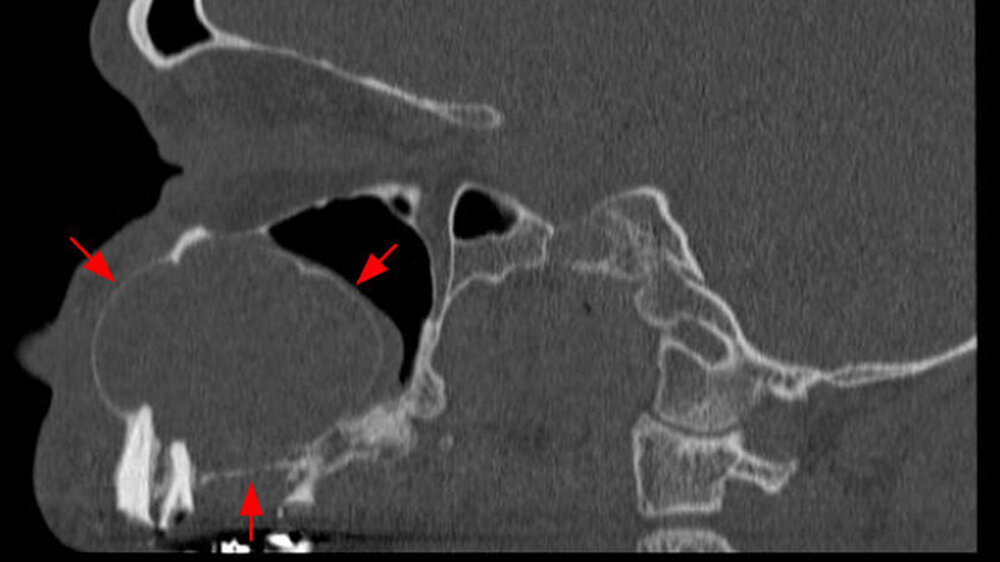

Bereits damals wurde vom Hauszahnarzt eine Entfernung der noch umschriebenen Raumforderung dringend empfohlen. Der Zahnfilm zeigte ein zystisches Geschehen in der Regio 24 und 25 (Abbildung 4). Zur aktuellen weiteren präoperativen Diagnostik wurde eine Computertomografie angefertigt. In den coronalen Schnitten ist die die Mittellinien überschreitende Raumforderung bis zum knöchernen Nasenboden unter Einbezug der linken Kieferhöhle deutlich zu sehen (Abbildung 5a). Man erkennt insbesondere in den sagittalen Schnitten, dass die Raumforderung über zwei Drittel der linken Kieferhöhle beansprucht (Abbildung 5b).

Auf den axialen Schnitten der Computertomografie ist sowohl die palatinale Ausdehnung wie auch die Einbeziehung der Oberkieferzähne im zweiten und teilweise ersten Quadranten gut zu erkennen (Abbildung 5c). Insgesamt stellt die diagnostische Bildgebung dar, dass es sich um einen verdrängenden, nicht destruierend-infiltrierenden Prozess handelt, der mit sehr hoher Wahrscheinlichkeit von der bereits vor sechs Jahren diagnostizierten Raumforderung in Regio 24 und 25 ausging. Als Verdachtsdiagnose konnte somit von einer Raumforderung zystischen Ursprungs ausgegangen werden.